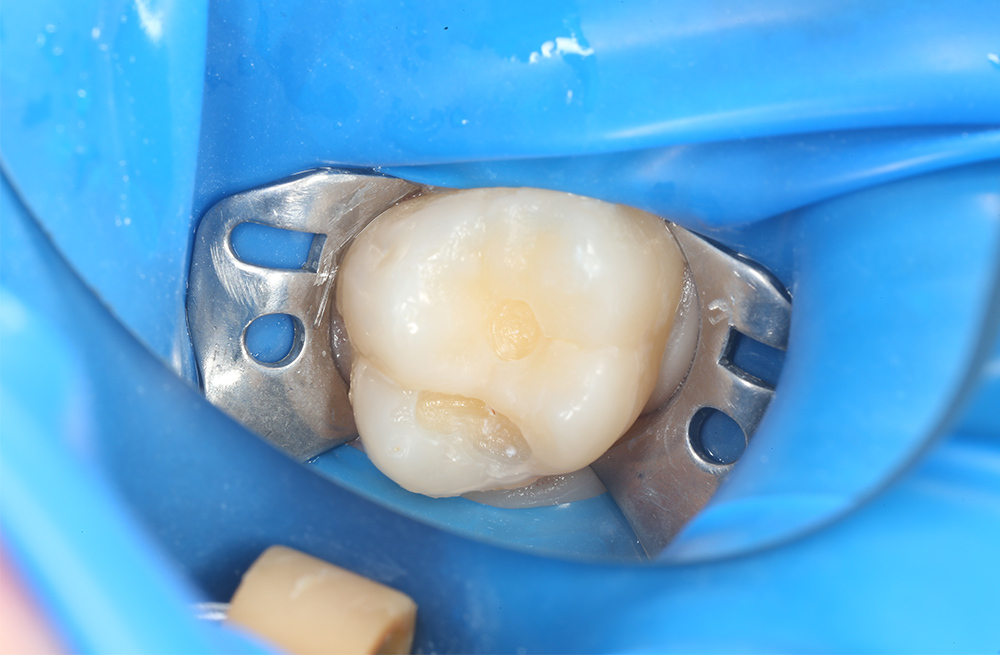

Пломбирование кариозного дефекта коренного зуба с сохранением здоровых тканей